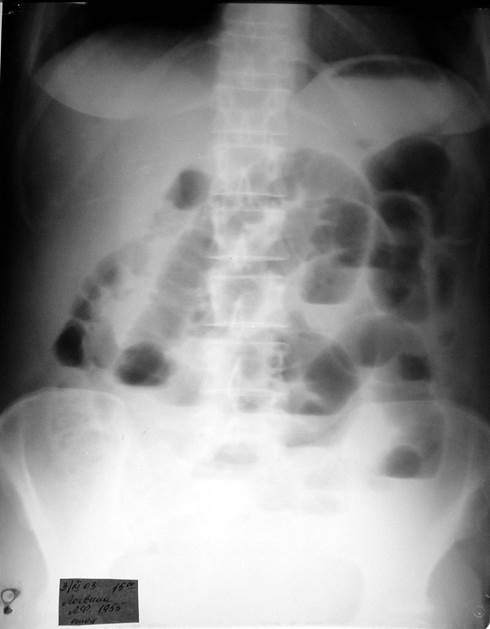

Вопросы к рис. 2:

1) Назовите рентгенологический метод исследования пациента, представленный на иллюстрации.

2) Назовите ведущий рентгенологический признак острой кишечной непроходимости и покажите его на рентгенограмме.

Рис. 2

1) Обзорная рентгенография брюшной полости.

2) На рентгенограмме определяются «чаши Клойбера» – вздутие петель кишечника с наличием скопления жидкости, образующей горизонтальные уровни.